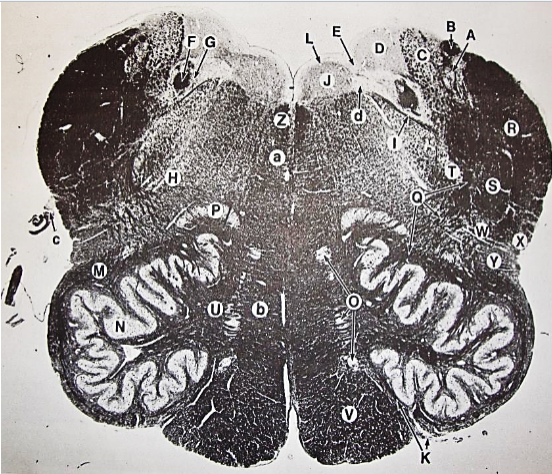

A

Lateral Cuneate nucleus

B

dorsal external arcuate fibers

C + D collectively

vestibular nuclei

C + D collectively

vestibular nuclei

E

dorsal motor nucleus of vagus nerve

F

solitary fasciculus

G

solitary nucleus

H

nucleus ambiguous

I

fascicles of glossopharyngeal nerve

J

hypoglossal nucleus

K

fascicles of hypoglossal nerve

L

dorsal longitudinal fasciculus

M

central tegmental tract

N

inferior olivary nucleus

R

inferior cerebellar peduncle

S

spinal trigeminal tract

T

spinal trigeminal nucleus

U

ventral trigeminothalamic tract

V

pyramidal (corticospinal) tract

W

rubrospinal tract

X

anterior spinocerebellar tract

Y

spinal lemniscus

Z

medial longitudinal fasciculus

a

tectospinal tract

b

medial lemniscus

c

vagus nerve

d

inferior salivatory nucleus

A + B collectively

vestibular nuclear complex

D

solitary fasciculus

E

solitary nucleus

F

nucleus ambiguous

G

fascicles of glossopharyngeal nerve

H

spinal trigeminal tract

I

spinal trigeminal nucleus

J

ventral trigeminothalamic tract

K

central tegmental tract

L

interior olivary nucleus

O

inferior cerebellar peduncle